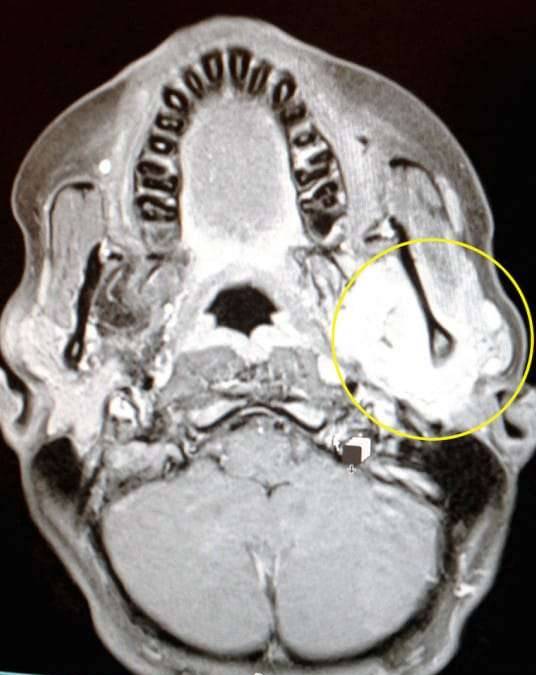

▼然而最终肿块却越来越大,因此瑞秋带着娜迪亚直奔急诊室,在做了MRI扫瞄后,娜迪亚脸上的肿块竟然是横纹肌肉瘤(rhabdomyosarcoma),一种极为罕见的恶性肿瘤,也就是癌症。

▼娜迪亚脸上的肿瘤在经过扫瞄后发现其实比肉眼看到的还要巨大。